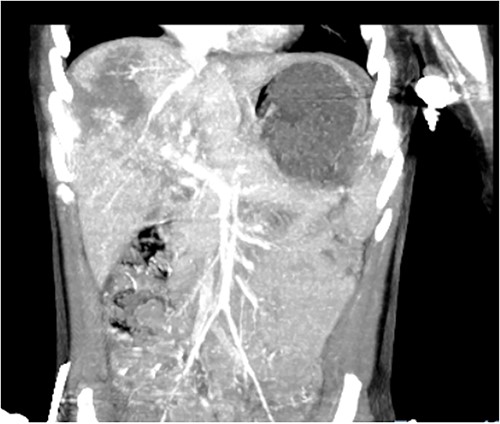

Computed tomography (CT) of the head and spine showed no other injuries. CT chest, abdomen, and pelvis showed a femoral neck fracture, grade IV liver injury, grade II splenic injury, and a fracture of the left iliac wing (Figs 1 and 2), along with a left sided bladder hematoma secondary to a pubic ramus fracture (Fig. 3). Interventional radiology was consulted to evaluate the liver and splenic injuries.